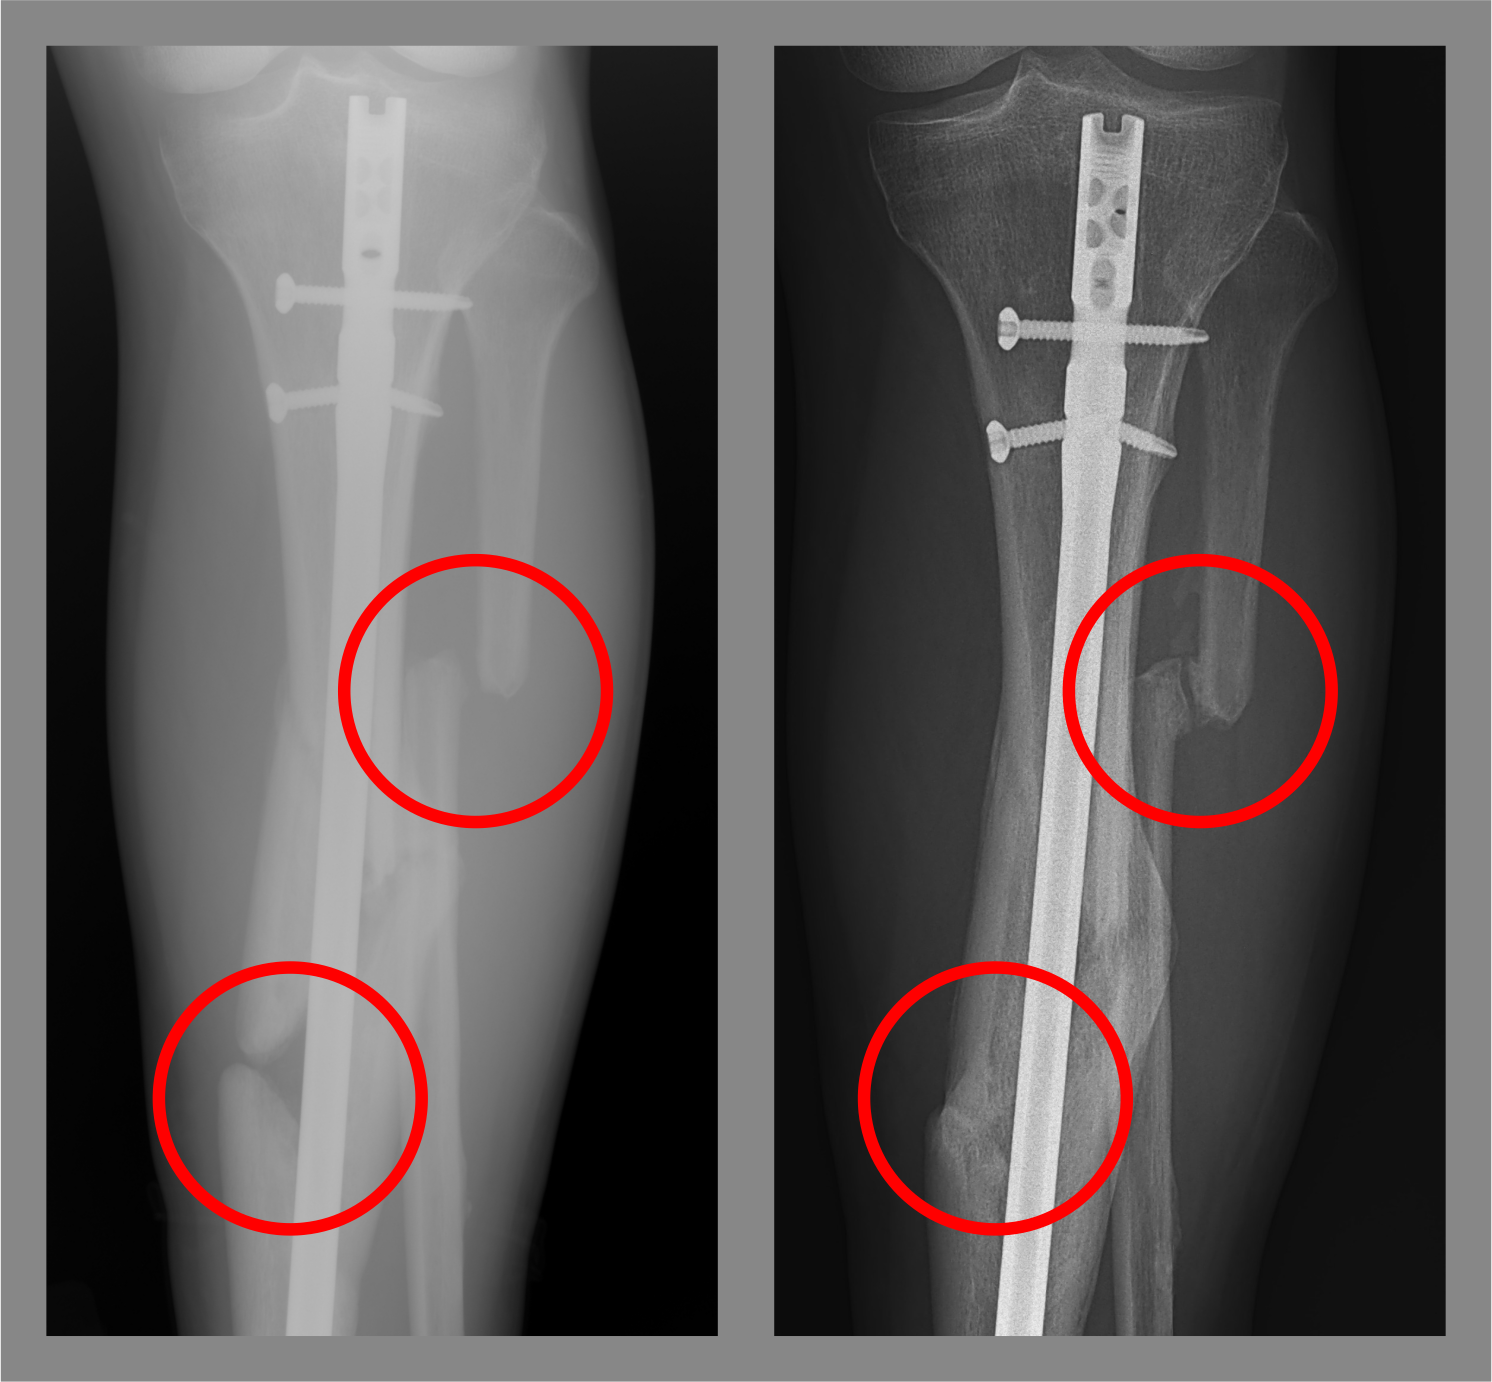

Jeff's leg is still broken but is pain-free

Image on the left is Jeff's x-ray from 2009 and the image on the right is from 2021.

In 2009, during a period of extreme discomfort, Jeff told his orthopedic surgeon he wished the leg could be removed. Years later, he still has the same injury but continues to live an active lifestyle.